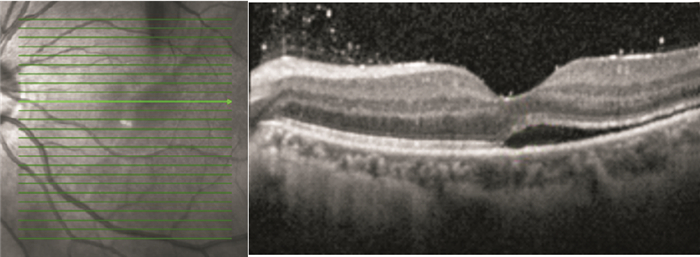

手術后1、3、6、12個月,BCVA 1.0者分別為1、8、11、15只眼。手術后6個月BCVA 0.15~1.0,平均BCVA0.59±0.29;手術后12個月,BCVA 0.15~1.0,平均BCVA 0.65±0.28。手術后6、12個月平均BCVA比較,差異無統計學意義(t=-0.636, P=0.529)。手術后12個月,視網膜下液吸收者BCVA 0.3~1.0,平均BCVA 0.68±0.34。其中,視網膜微結構正常者0.86±0.14;神經上皮層黃斑囊樣水腫者0.52±0.12;IS/OS斷裂者0.55±0.08;IS/OS和ELM斷裂者0.44±0.11。視網膜下液殘留者BCVA 0.15~1.0,平均BCVA 0.57±0.40,其中,BCVA 1.0者2只眼(圖 3)。視網膜微結構正常者、神經上皮層黃斑囊樣水腫者、IS/OS斷裂者、IS/OS和ELM斷裂者之間平均BCVA比較,差異有統計學意義(F=52.42,P<0.05)。視網膜下液殘留者平均BCVA與視網膜下液吸收者之間比較,差異有統計學意義(t=-5.747, P=0.000)。

患眼手術后6個月OCT像。視網膜下仍存在積液

患眼手術后6個月OCT像。視網膜下仍存在積液

手術后1、3、6、12個月,BCVA 1.0者分別為1、8、11、15只眼。手術后6個月BCVA 0.15~1.0,平均BCVA0.59±0.29;手術后12個月,BCVA 0.15~1.0,平均BCVA 0.65±0.28。手術后6、12個月平均BCVA比較,差異無統計學意義(t=-0.636, P=0.529)。手術后12個月,視網膜下液吸收者BCVA 0.3~1.0,平均BCVA 0.68±0.34。其中,視網膜微結構正常者0.86±0.14;神經上皮層黃斑囊樣水腫者0.52±0.12;IS/OS斷裂者0.55±0.08;IS/OS和ELM斷裂者0.44±0.11。視網膜下液殘留者BCVA 0.15~1.0,平均BCVA 0.57±0.40,其中,BCVA 1.0者2只眼(圖 3)。視網膜微結構正常者、神經上皮層黃斑囊樣水腫者、IS/OS斷裂者、IS/OS和ELM斷裂者之間平均BCVA比較,差異有統計學意義(F=52.42,P<0.05)。視網膜下液殘留者平均BCVA與視網膜下液吸收者之間比較,差異有統計學意義(t=-5.747, P=0.000)。

患眼手術后6個月OCT像。視網膜下仍存在積液

患眼手術后6個月OCT像。視網膜下仍存在積液

本組患者手術后2周,雙目檢眼鏡聯合B型超聲檢查見視網膜復位;OCT檢查提示視網膜下仍有部分積液,直至手術后12個月,視網膜復位率亦未達到100%。分析其主要原因,OCT分辨率較B型超聲高近10倍,可獲得10 μm的高分辨率,能更清楚的顯示視網膜各層結構,發現微小異常。手術后12個月OCT檢查示視網膜下液吸收率為88.1%,與Wolfensberger和Gonvers[2]報道的手術后1年11.0%的患者殘存黃斑下積液的發生率相當。有文獻報道,影響視力預后的主要因素有視網膜脫離時間、神經上皮層囊樣水腫、視網膜下液殘留、IS/OS損傷及ELM破壞[3]。視網膜脫離時間影響手術后視力的恢復已成為共識[1, 4, 5],但黃斑積液對視力的影響尚無定論[6]。Wakabayashi等[7]認為黃斑積液對手術后視力無明顯影響,而本組患者手術后12個月,黃斑處視網膜積液明顯影響手術后視力。其原因主要是黃斑下積液導致視網膜神經層和視網膜色素上皮(RPE)層之間的物質轉運發生障礙。及時發現并手術,視力預后較好;積液時間過長,光感受器細胞外節的代謝受影響,視力預后差。